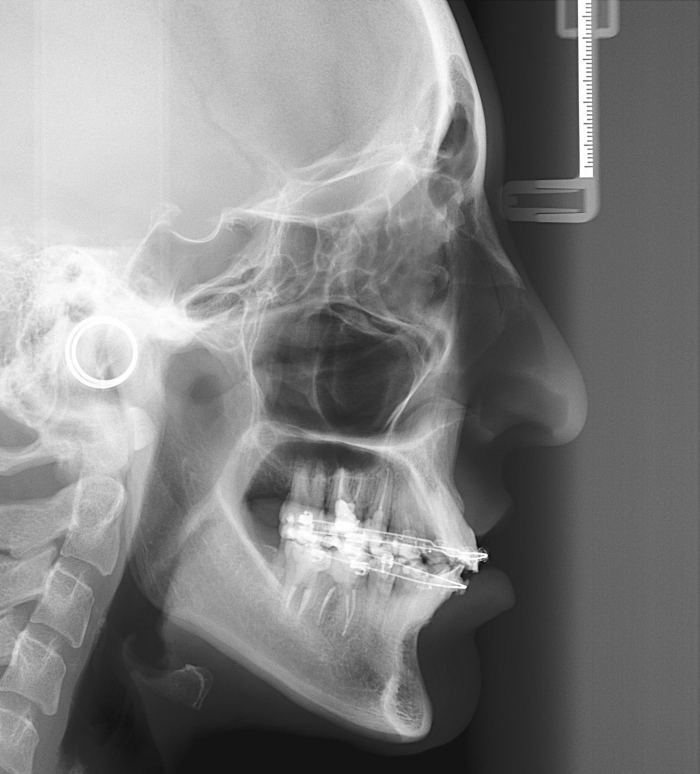

Telerradiografia inicial

Telerradiografia após a cirurgia